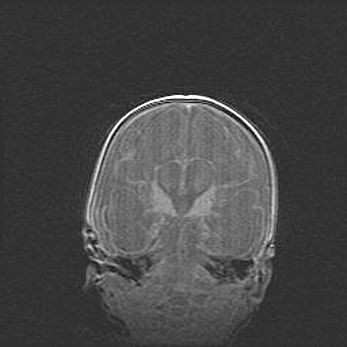

Мальформация Денди-Уокера. Киста задней черепной ямки.

Агенезия мозолистого тела.

Возраст: 2,5 месяца

Вес: 2420 г

Пол: женский

Окружность головы: 37 см

Срок гестации: 32 недели

Мальформация Денди—Уокера — редкий вид патологии ЦНС, представляющий собой врожденный порок развития каудального отдела ствола и червя мозжечка, ведущий к неполному раскрытию срединной (Мажанди) и латеральных (Лушка) апертур IV желудочка мозга. Для этогно синдрома характерна триада симптомов: гипотрофия червя мозжечка и/или полушарий мозжечка, кисты задней черепной ямки, гидроцефалия различной степени. В 70% случаев порок сочетается и с другими аномалиями головного мозга, в частности с агенезией мозолистого тела.